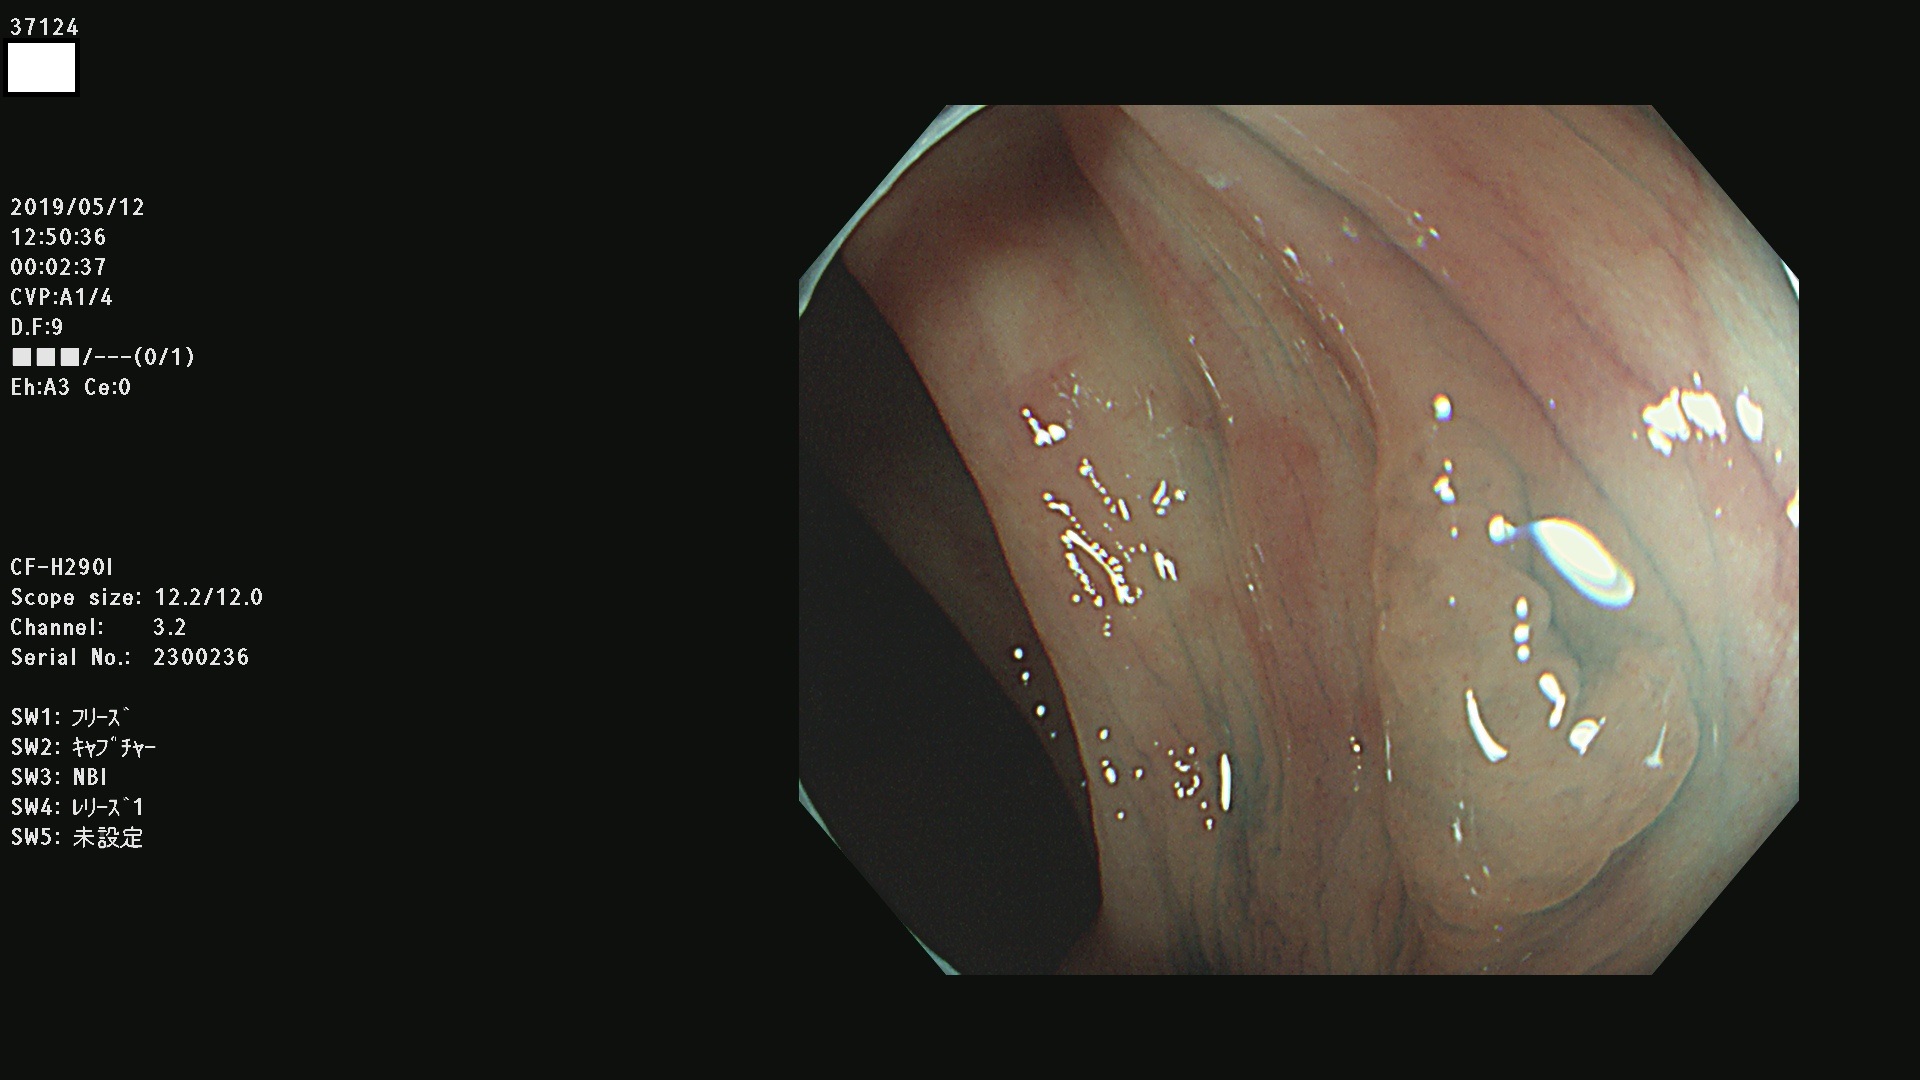

37100 37101 37102 37104 37106 37108 37110 37111 37112 37113 37115 37118(SSAPのみ) 37120 37122 37123 37124 37127(SSAPのみ) 37128(SSAPのみ) 37131 37132 37133 37134 37135 37139 37141 37142 37143 37144(SSAPのみ) 37145 37147(SSAPのみ) 37148 37149 37150 37153 37154 37157 37159 37161 37162 37163 37164 37165 37166 37167 37168 37169 37170 37171 37172 37173 37175(SSAPのみ) 37176 37177 37178 37180(SSAPのみ) 37181 37184 37185 37186 37187 37188 37189 37190 37192 37194 37197 37198

発見困難で危険性の高い平坦型病変(上記100名より抽出)